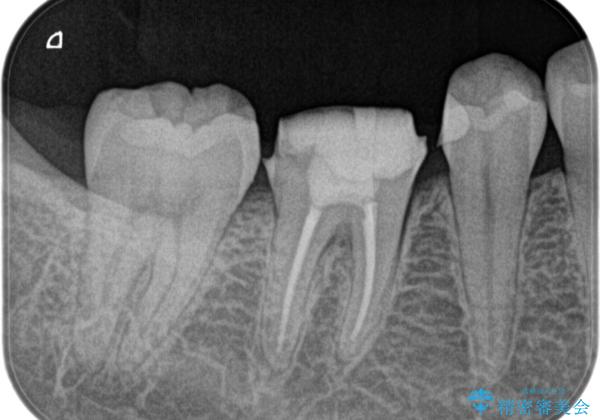

- 奥歯がズキズキ痛いことを主訴に来院されました。

検査の結果、診断を症候性不可逆性歯髄炎、症候性根尖性歯周炎とし抜髄を行っております

根管充填はhydraulic condensation techniqueにて行なっております。

シーラーはWell pulp ST 使用